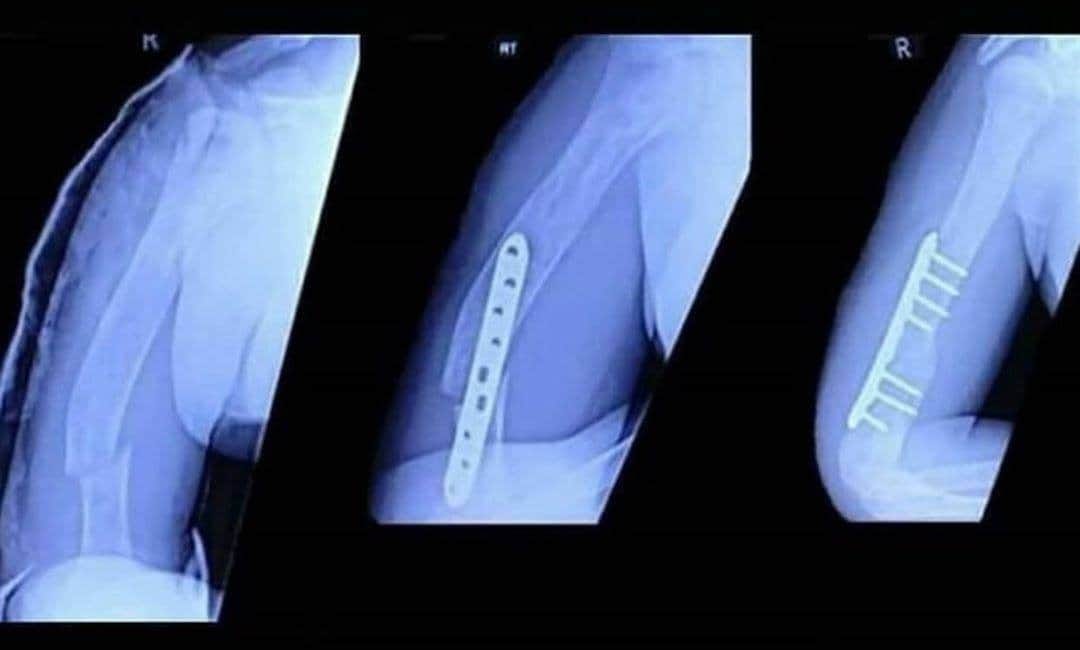

Marc Marquez上週日在西班牙Jerez站上演了一場驚天地動鬼神的精彩表現,但很不幸的是Marquez最終以嚴重的Highside摔車退場,更令人擔憂的是摔車事故讓Marc Marquez的右手肱骨骨折;不過近日傳出好消息,Marc Marquez的手術相當成功,並且預期最快在8月9日的MotoGP捷克Brno站就能復出參賽。